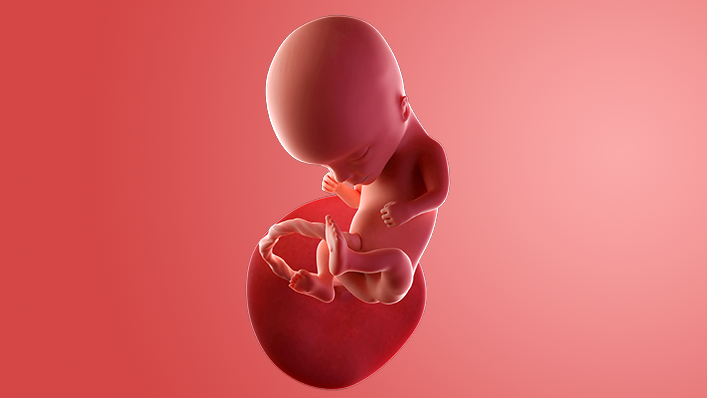

What does my baby look like?

Your baby, or foetus, is now 5.4cm long from head to bottom, which is about the size of a plum.

The internal organs and muscles have grown, and the heartbeat can be picked up on an ultrasound scan. The skeleton is made up from tissue and hardening into bone.

The sex organs have formed, although most scans will not be able to tell your baby's sex until later.